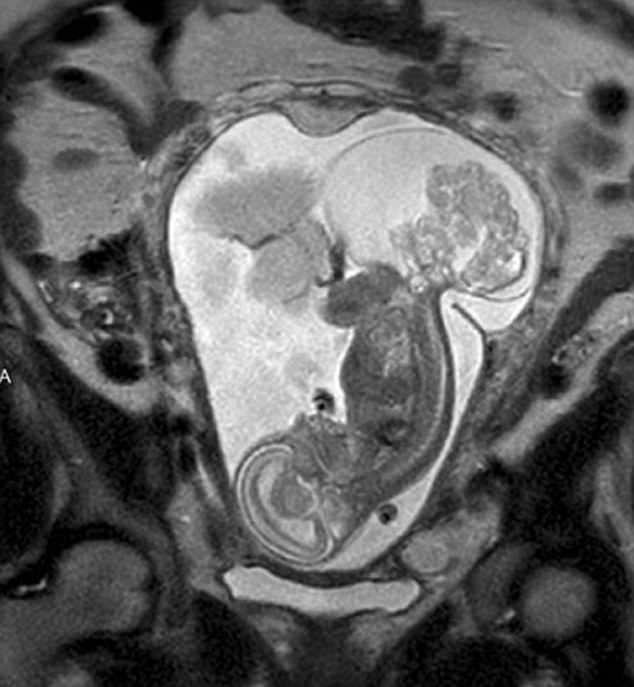

【環(huán)球網(wǎng)綜合報道】據(jù)英國《每日郵報》10月23日報道,美國得克薩斯州布蘭諾市的女子瑪格麗特·伯默(Margaret Boemer)懷孕16周時去做產(chǎn)檢,不幸被告知胎兒尾骨上長有腫瘤,她與醫(yī)生商量后決定先將胎兒取出進行腫瘤切除手術(shù),再將其送回子宮繼續(xù)孕育。最終手術(shù)圓滿成功,12周后胎兒足月出生。

瑪格麗特稱自己當時聽到產(chǎn)檢結(jié)果時十分害怕!搬t(yī)生說寶寶長了骶尾部畸胎瘤。我們很震驚,很害怕,因為我們根本不知道這個什么瘤到底意味著什么!彪S著時間流逝,腫瘤越來越大,胎兒滿23周時腫瘤已危及其性命。醫(yī)生告訴瑪格麗特,若想胎兒存活,只能將胎兒取出進行手術(shù),然后再放回子宮,否則只能立即終止孕期。“這很容易做決定:讓腫瘤奪去孩子性命,或是給孩子存活的機會。我們當然選擇后者!爆敻覃愄卣f。

醫(yī)生將胎兒取出20分鐘后,便放回母體子宮。12周后,寶寶足月出生,敻覃愄胤Q:“這可以說是她的第二次出生了。只要她有機會活下來,我愿意承受所有風險!(實習編譯:高睿 審稿:朱盈庫)